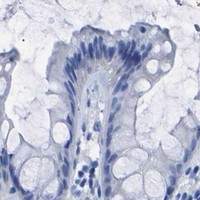

Enhanced - Independent antibodies

Protein distribution across 45 tissues similar between the independent antibodies HPA018407 and HPA018415.

Colon

Kidney

Liver

Urinary bladder